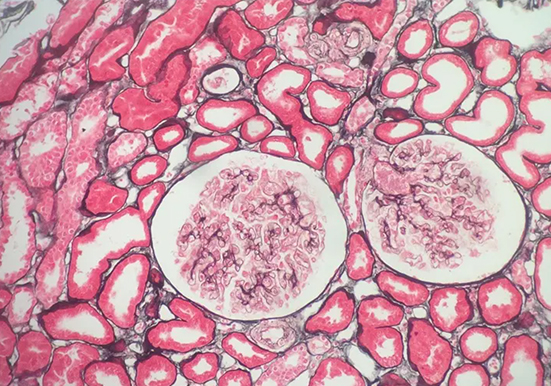

刚果红染色是一种常用的生物染色方法,以下是关于它的详细介绍:

染色原理:主要依赖于其与蛋白质及其他生物大分子的亲和性,通过静电吸引、氢键等作用力与样品中的不同组分发生相互作用,使样品呈现出特定的颜色。